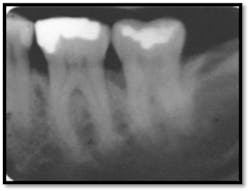

#19 presents with Class I furcation involvement

#18 presents with a mesial vertical defect and Class II furcation involvement